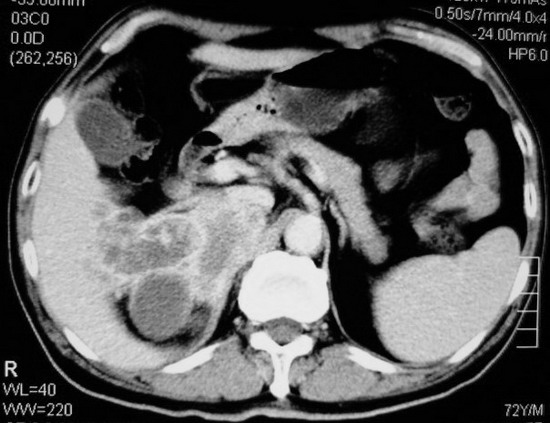

以下是引用杀毒软件在2008-11-17 19:15:00的发言:[br]考虑------右肾癌合并肾静脉---同侧肾上腺受侵可能性大

以下是引用zjzjr在2008-11-17 20:45:00的发言:[br]考虑------右肾癌合并肾静脉---同侧肾上腺受侵可能性大及腹膜后淋巴结转移.